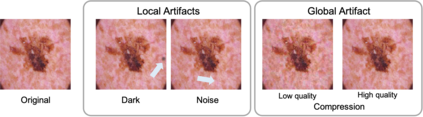

To safely deploy deep learning-based computer vision models for computer-aided detection and diagnosis, we must ensure that they are robust and reliable. Towards that goal, algorithmic auditing has received substantial attention. To guide their audit procedures, existing methods rely on heuristic approaches or high-level objectives (e.g., non-discrimination in regards to protected attributes, such as sex, gender, or race). However, algorithms may show bias with respect to various attributes beyond the more obvious ones, and integrity issues related to these more subtle attributes can have serious consequences. To enable the generation of actionable, data-driven hypotheses which identify specific dataset attributes likely to induce model bias, we contribute a first technique for the rigorous, quantitative screening of medical image datasets. Drawing from literature in the causal inference and information theory domains, our procedure decomposes the risks associated with dataset attributes in terms of their detectability and utility (defined as the amount of information knowing the attribute gives about a task label). To demonstrate the effectiveness and sensitivity of our method, we develop a variety of datasets with synthetically inserted artifacts with different degrees of association to the target label that allow evaluation of inherited model biases via comparison of performance against true counterfactual examples. Using these datasets and results from hundreds of trained models, we show our screening method reliably identifies nearly imperceptible bias-inducing artifacts. Lastly, we apply our method to the natural attributes of a popular skin-lesion dataset and demonstrate its success. Our approach provides a means to perform more systematic algorithmic audits and guide future data collection efforts in pursuit of safer and more reliable models.